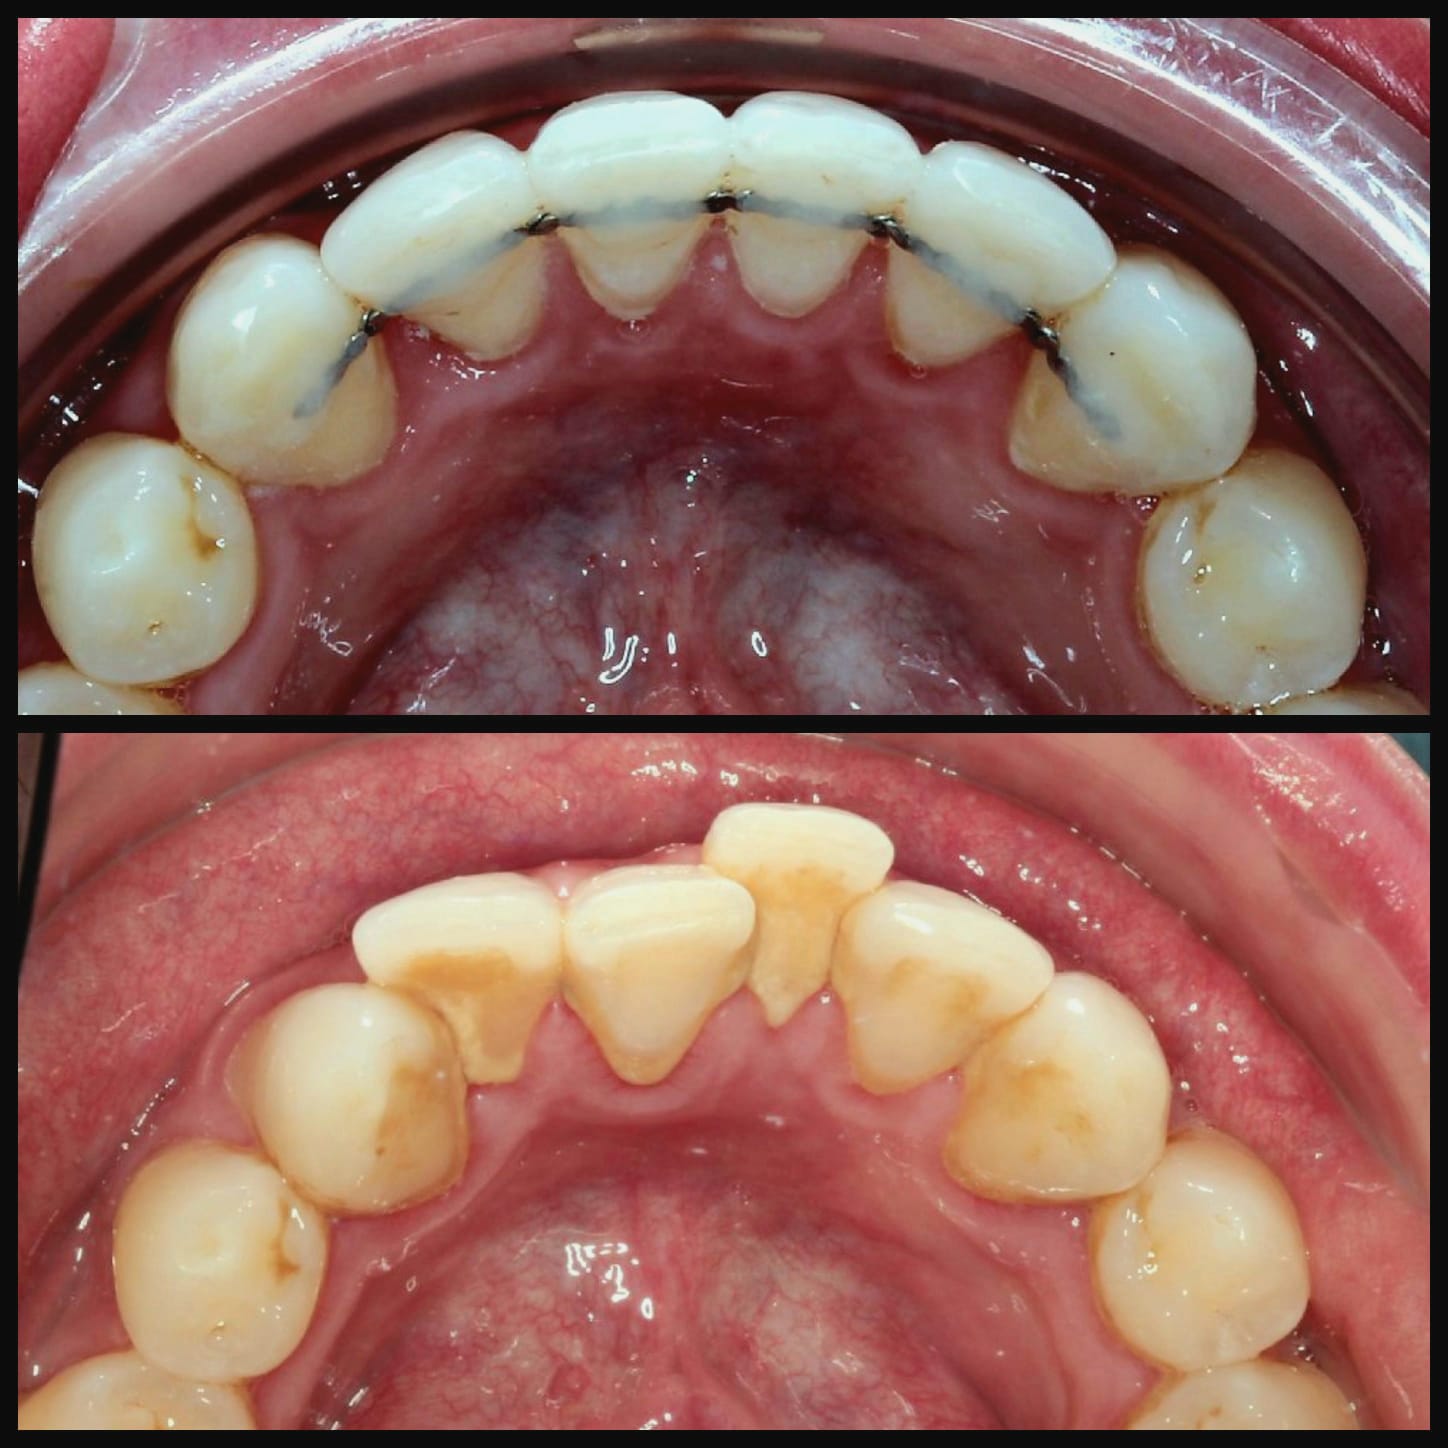

Invisalign is a well-known system for straightening teeth in the most discreet way. It works by using a series of clear aligners that fit comfortably over the teeth to gently move them into the desired position over time. There are no fixed brackets or wires used, in fact, the aligners are completely removable.

Invisalign is a clear alternative to traditional metal braces, offering a discreet and convenient way to achieve a straighter smile. Unlike traditional braces, Invisalign aligners are removable and nearly invisible, allowing you to eat, drink, and live your life without restriction. With Invisalign, you can straighten your teeth without the hassle and self-consciousness of metal braces.